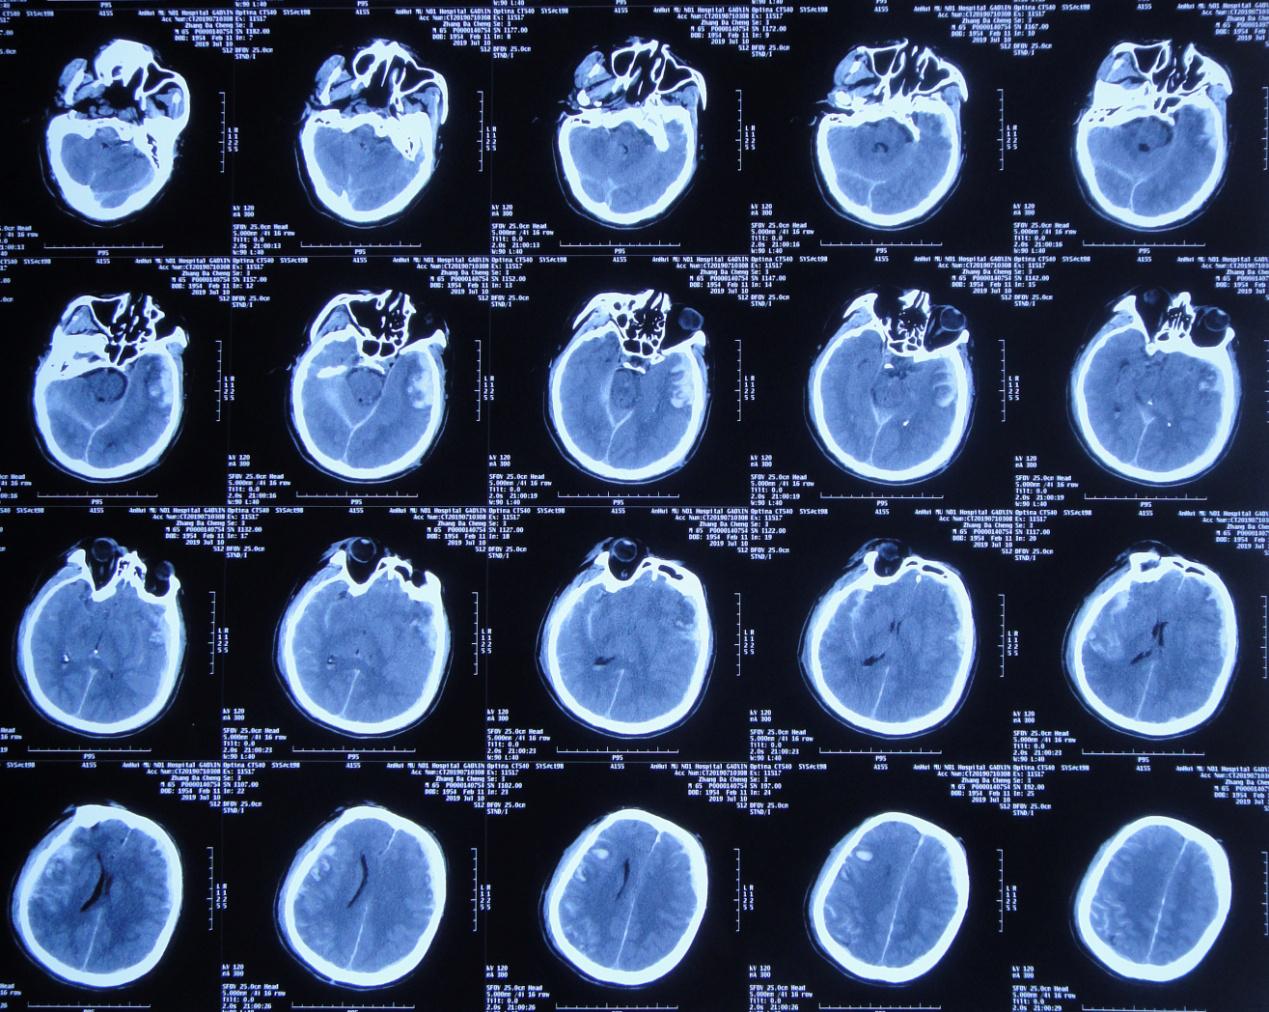

一、李小勇脑脊液科入院前病史

患者2019年7月10日骑电动自行车不慎与大货车相撞,当时意识模糊,可简单对答,四肢可见活动。由120急送至当地安徽省六安市某医院,行头颅CT示大脑多发挫伤(片子丢失),给予甘露醇等脱水治疗,效果差,意识明显加重,呼之不应,呈昏迷状态。当日急转入上级的安徽省某知名省级三甲医院,行头颅CT( 图-1 )示左颞叶脑挫伤伴血肿形成,右额叶脑挫伤,蛛网膜下腔出血,脑疝。

图-1: 2019年7月10日术前头颅CT

当日急诊行“左颞叶血肿清除+去骨瓣减压术”,术后当日复查头颅CT( 图-2 )呈术后改变。术后药物营养脑细胞、降颅压、消炎等治疗。

图-2: 2019年7月10日术后头颅CT